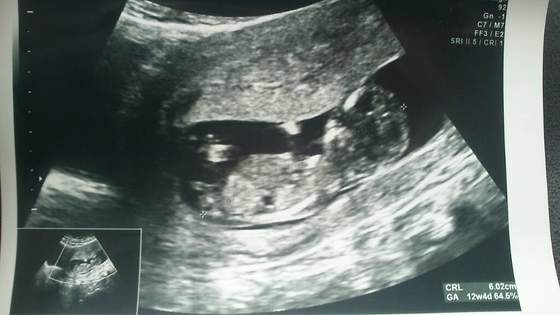

A to jeszcze mój babel :-)

Załączniki

• 1405091195422.jpg

1405091195422.jpg

21,9 KB · Wyświetleń: 66